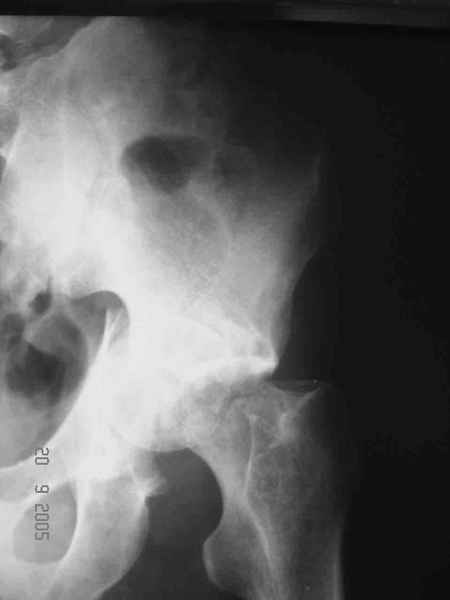

Привет! Вот недавно прооперировали похожий на ваш случай - впадина + шейка (правда у нас впадина поперечный+задний край). После травмы прошло 4 недели. мужчине 46 лет. С такой комбинацией все показания к первичному протезированию. Морально и технически мы к этому уже созрели.Но больной не собрал денег на протез. Выполнили остеосинтез впадины и шейки, прекрасно понимая, что головка вскоре рассосется, мы хотя бы надемся что к этому времени таз срастется, как говорится создали все условия для дальнейшего протезирования (может, и протез в последующем подешевле будет, в смысле, без укрепляющего кольца?). Привет Рункову!

Согласен, можно было и подлиннее. Доступ такой же - чрезвертельный, только разрез кожи прямой (а не Y, чего то я разницы не ощущаю). Головка была абсолютно свободной (то есть во время остеосинтеза таза лежала в стакане и не мешалась). Шансов, что она прирастет 0,00001%. Хотели даже выбросить, но привинтили как временный биологический протез (читай свободный трансплантат), чтоб на период срастания таза бедро проксимально не ушло (может ортопеды потом спасибо скажут). Ну а у вас первичное протезирование при переломе впадины тоже пока полько в планах?